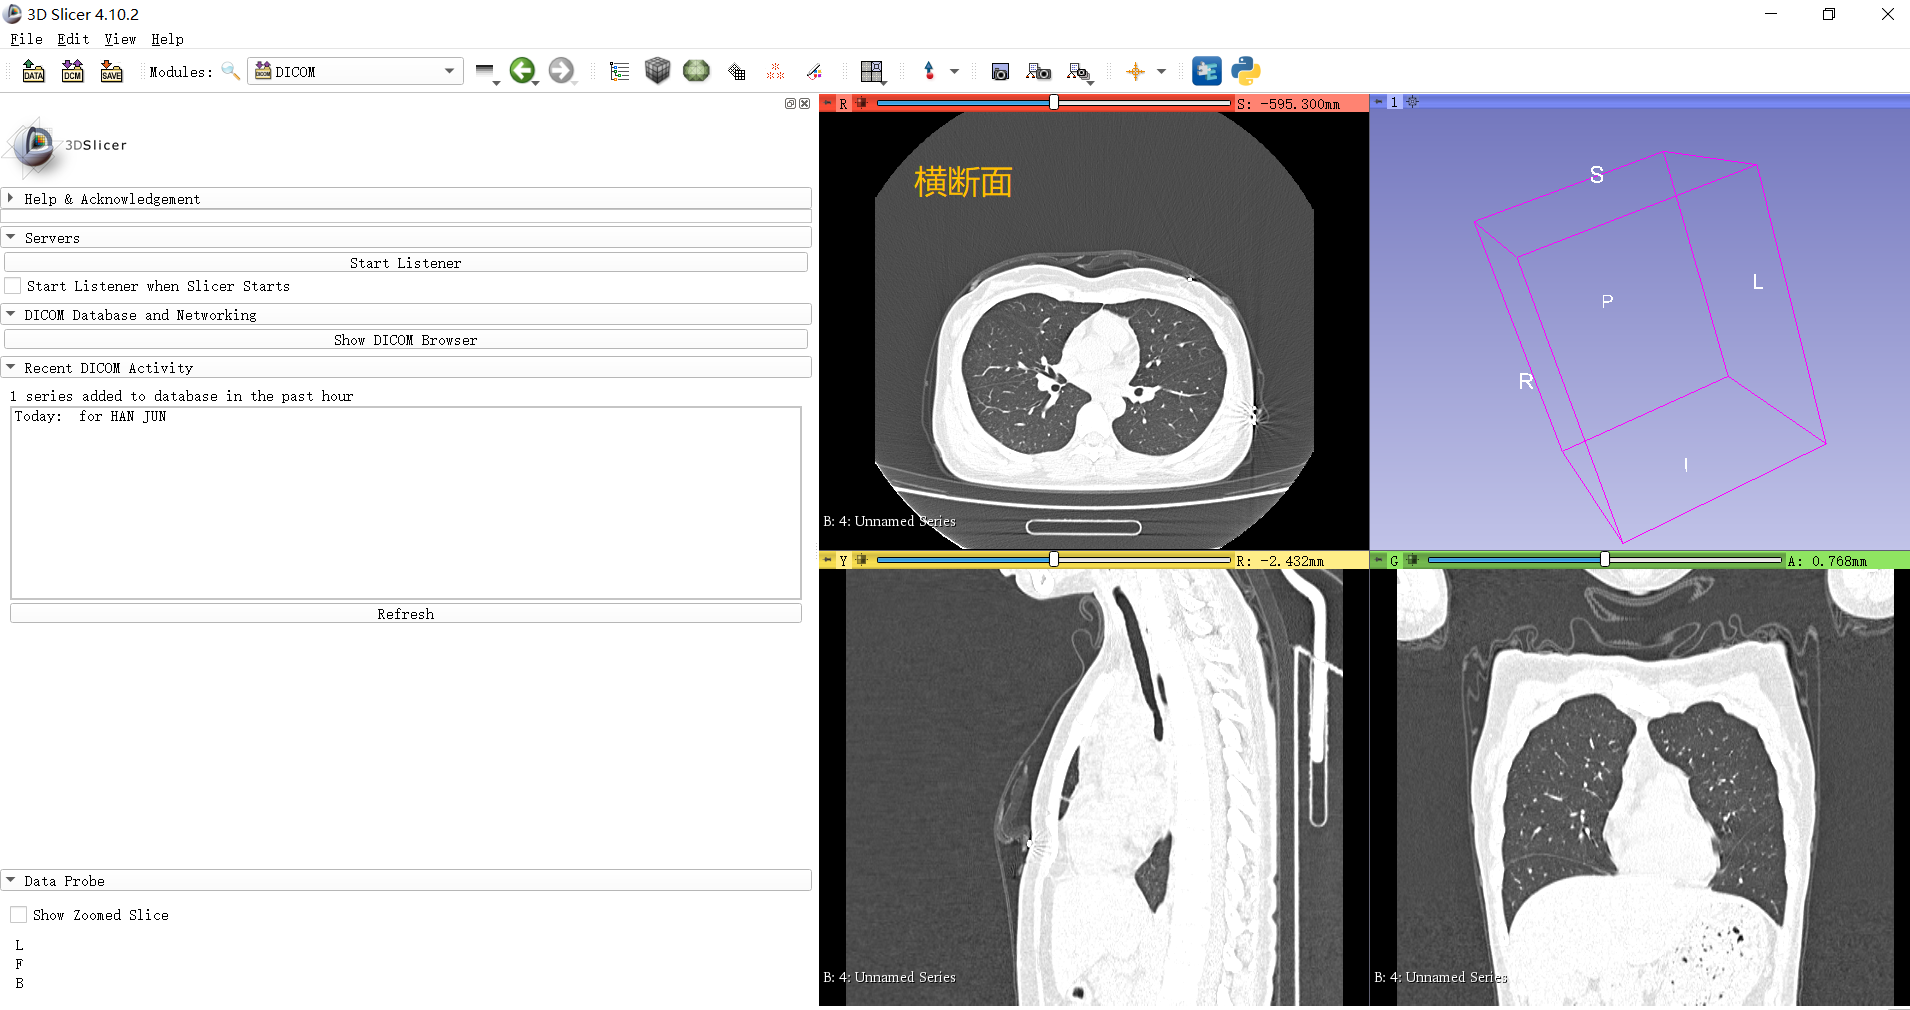

点击load之后,CT的三个维度的2D切片会出现在3D slicer中,退出DICOM Brower。3D slicer的左上视图为CT的横断面,我们在横断面中进行标注:

切换3D slicer的功能模块至Segment Editor:

上图蓝色框内,Segmentation表示本次label volume的名字,Master volume表示右边正在显示的Volume的名字,按默认的就行。 -